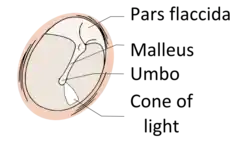

![]() پرده گوش راست که در اتوسکوپ دیده میشود. | |

در انسان، پرده گوش کمی مخروطی شکل است و مساحت آن در حدود ۸۵ میلیمترمربع است. پرده گوش از دو بخش تشکیل شده است. بخش نرم پرده یا پارس فلاسید و بخش سفت پرده یا پارس تنسا که بخش سفت پرده pars tensa از فیبرهای کلاژن شعاعی و دایرهای تشکیل شدهاست. این فیبرها با لایههای بافت همبند به هم متصل شده و از خارج با یک لایه روپوستی از بافت پوششی صدفی که در امتداد پوست مجرای گوش خارجی قرار دارد پوشانیده شدهاند. سطح داخلی پرده گوش را نیز لایهای مخاطی از سلولهای صدفی مژکدار پوشانیده است. وضعیت پرده گوش عامل مهمی در تغییر شدت یا غربالگری طیف محرک صوتی محسوب میشود و بنابراین اطمینان از سلامت آن حایز اهمیت است.